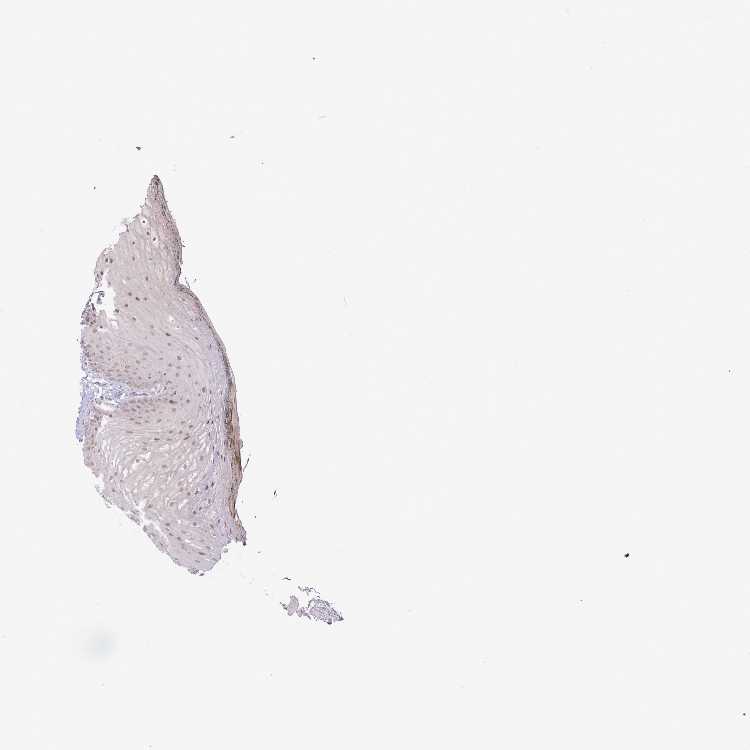

TISSUE PRIMARY DATA ORAL MUCOSA Show tissue menu

ORAL MUCOSA - Antibody stainingi

Antibody staining in the annotated cell types in the current human tissue is reported as not detected, low, medium, or high, based on conventional immunohistochemistry profiling in selected tissues. This score is based on the combination of the staining intensity and fraction of stained cells.

Each image is clickable and will lead to virtual microscopy that enables deeper exploration of all samples and also displays staining intensity scores, fraction scores and subcellular localization as well as patient and tissue information for each sample.

Antibody HPA050320

Squamous epithelial cells Medium